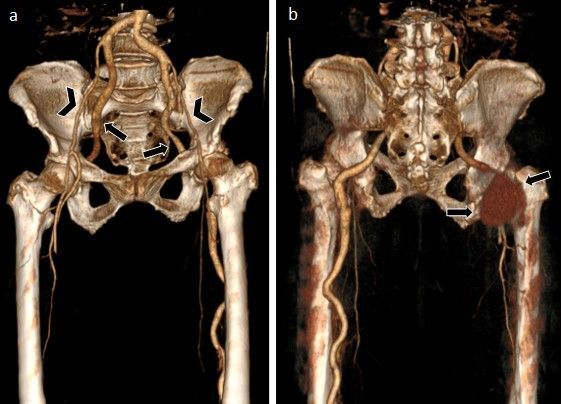

Persistent sciatic artery is a rare congenital anomaly, with few cases described in the literature. This study presents a case of this embryological variation observed in a patient's lower limb circulatory system. The anatomical description is based on a review of medical records and imaging exams. This case report describes a 63-year-old female patient admitted to the emergency department complaining of severe pain in the right lower limb, with a cold, pale extremity and ecchymosis on the dorsum of the foot. Duplex ultrasound showed no detectable flow in the anterior tibial and fibular arteries and a tardus parvus pattern in the posterior tibial artery. The patient developed loss of movement and fixed cyanosis in the right foot and was referred for urgent thromboembolectomy. However, adequate reperfusion was not seen after the procedure. Angiotomography was performed on the first postoperative day, showing bilateral persistence of the sciatic artery, with aneurysmal degeneration, partially thrombosed, and no opacification of the arterial system downstream of the aneurysm. By the third postoperative day, the patient had developed areas of dry necrosis in the limb, with no perfusion to the ankle, and underwent transfemoral amputation. Despite being a rare condition, it is of great clinical importance because of the high complication rates.